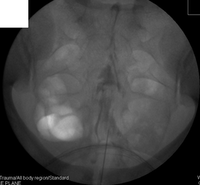

Using a specialised X-ray machine called a fluoroscope, the needle is placed using X-ray guidance. Correct needle placement is confirmed using radiological dye called ‘contrast’, usually Omnipaque 240. This improves the effectiveness and safety of the injection.

Examples of joint injections requiring fluoroscopy include:-

Hip